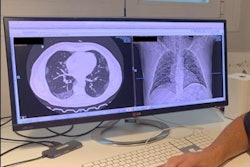

One of our most popular articles for the past week was a story on the shifting opinions regarding the value of CT as a first-line tool for diagnosing COVID-19. The conventional wisdom has been that CT should be avoided in favor of in vitro diagnostic (IVD) tests. But a new French report questions that advice. The authors believe that the low sensitivity of IVD tests creates an opening for CT in areas where COVID-19 is prevalent.

In other CT news, Austrian researchers presented a study at the European Respiratory Society International Congress on how CT can identify lung damage in COVID-19 patients that may have been missed by lung function tests. Get more stories like this in our CT Community.